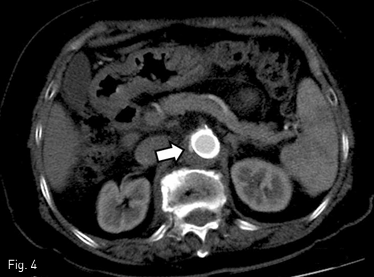

좌측 대퇴동맥을 천자하여 5 Fr sheath를 삽입하고 우측 대퇴동맥을 천자하여 8 Fr sheath를 삽입하였다. 좌측 대퇴동맥을 통하여 5 Fr pigtail catheter를 상부 복부 대동맥에 위치시킨 후 대동맥 조영술을 시행하였다. 낭성 동맥류가 상장간막동맥 기시부의 뒤쪽에 있었고 우측 신장동맥의 기시부에는 국소협착이 있었다. 5Fr GLIDE catheter with Sim 1 shape (Terumo Medical Corp., Somerset, NJ)와 0.035인치 유도철사를 이용하여 우측 신장동맥을 선택한 후 0.035인치 stiff 유도철사로 교체하였다. 8-Fr RDC Vista Brite Tip guide catheter (Cordis, Miami Lakes, FL)를 삽입 후 0.018인치 유도철사로 교체하고 5 mm x 19 mm balloon-expandable bare metal stent (Express SD; Boston Scientific, Marlborough, MA)를 우측 신장동맥 협착부에 설치하였다. 이후 0.035인치 stiff 유도철사를 대동맥에 위치시킨 후 25 mm x 100 mm MFM stent (Cardiatis, Isnes, Belgium)를 낭성 동맥류를 중심으로 위치시켜 상부대동맥 전반에 걸쳐 설치하였다. 시술후 시행한 혈관조영 영상에서 스텐트 내부 및 하방의 혈류는 잘 유지되어 있고 복강 동맥, 상장간막동맥 그리고 양측 신장동맥 등의 혈류도 잘 유지되고 있었다. 그리고 복부 대동맥류 내부로의 혈류도 남아 있었다 (Fig. 2).

Fig 2

Abdominal aortography shows a MFM stent along the entire abdominal aorta and an endovascular stent at the right proximal renal artery (arrowhead) with favorable patency. All visceral arteries are patent. Residual flow is noted within the saccular aneurysm (arrow).